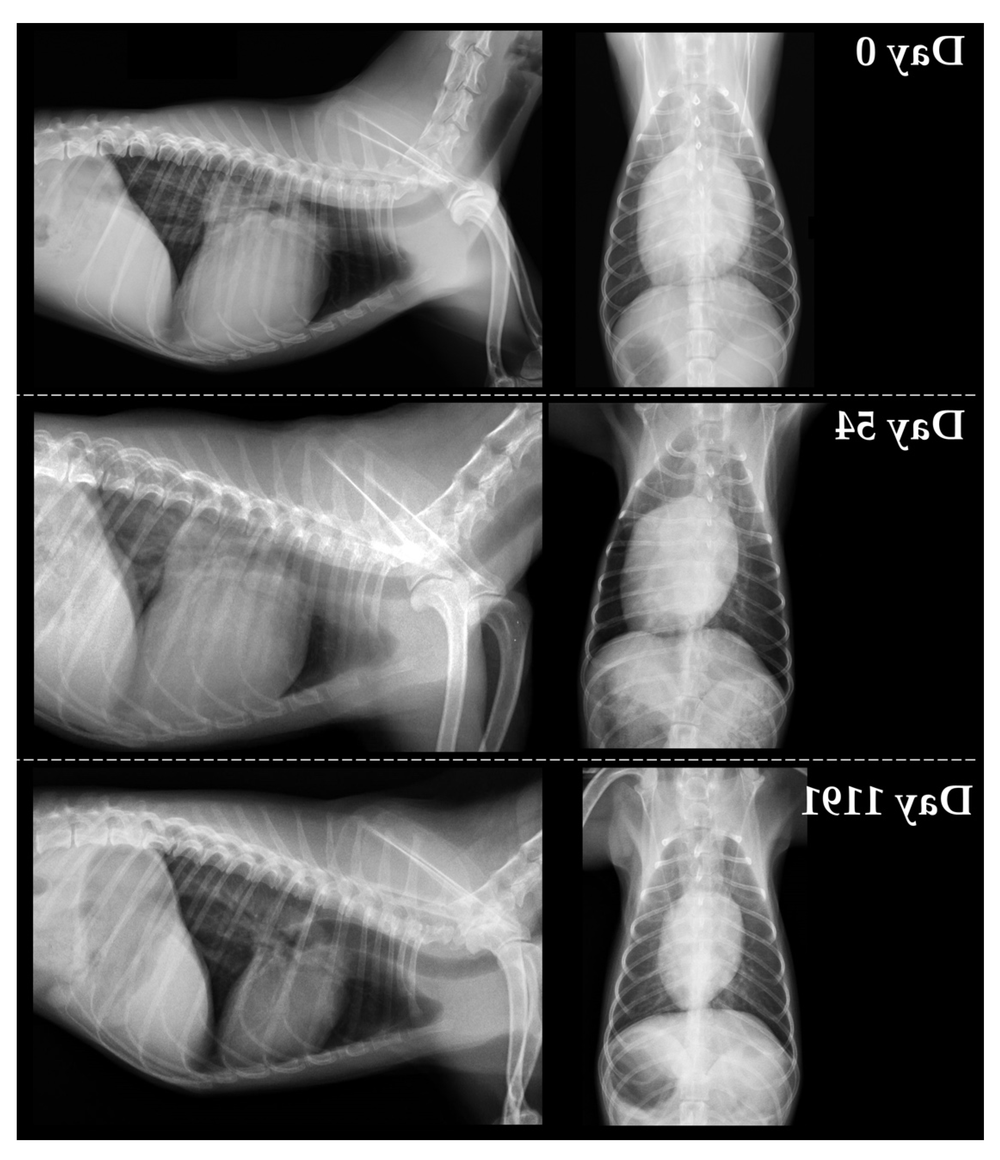

• Chest X-rays to look for heart enlargement and fluid in or around the lungs

These are not “extra for the sake of it”. They help separate primary cardiomyopathy from other causes of thickened walls, and they help stage risk, which is what guides treatment decisions.1, 8